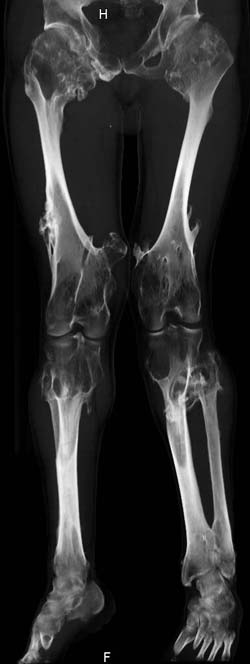

Oбратился больной 30 лет с хондродисплазией, множественными деформациями и экзостозами. Сгибательно-приводящие контрактуры Т/Б сустав, поясничный лордоз.

Интелектуально развит, работает програмистом. Болей нет. Анализы крови в пределах нормы, понижен кальций (общий Ca 1.62, N от 2.3 до 2.75;ионизорованный 0.67, N от 0.7 до 1.07) и щелочная фосфотаза -7.9. По данным КТ, оптическая плотность диафизов 150 - 200 NU (N в его возрасте 300 -350NU) метафизарный остеопороз от 100NU до отрицательных величин - 80 NU.

Планирую поэтапно, сначала справа, произвести вальгизирующе-антекурвационную остеотомию в подвертельной области бедра, соответственно варизирующую на голени, фиксация фрагментов спице - стержневым аппаратом Илизарова. Одновременно удалить большой экзостоз в области конен. сустава

30 years old male with chondrodysplasia and multiple exostoses admitted.Multilevel deformities, flexion-adduction limitation of hip ROM, lumbar lordosis. Intellectually developed, working in some software company. Painless. Blood tests are normal, except low Calcium (total serum Ca 1. 62, N is 2.3 - 2.75; ionized 0.67 N is 0.7 -1.07) and low alkaline phosphatase 7.9. Diaphysis bone density is about 150 - 200 NU (N in his age is 300 - 350NU). Metaphis osteoporosis is from 100NU to minus 80 NU.

I am thinking about subtrochanteric valgization osteotomy of femur, varization osteotomy of tibia, fixation with Ilizarov - hybrid type external fixator, simultaneously removal of big exostosis in right knee area. But, before do something, I would like to know your valuable opinions. Myquestions are:

The x-ray is satisfactory for analysis. In The AP view, The knee and ankle should be exactly anterior and the patella should be facing forward, then we can measure the deformity in the AP. Another lateral view of the whole lower limb should be taken, so we can correct 6 dimensions (X, Y and Z axes and Alpha, Beta and Gamma rotation).

But it seemes to me that he has distal femoral valgus and may be also distal tibial. But anyway, we have to measure a good x-ray (lateral distal femoral angle, Medial proximal tibial angle and also the distal tibial angles).

Somtimes there are many deformities in the same lower limb. I do not like to make it sophistacted and correct everything, but just correcting the biggest deformity will make the alignment much better and the patient will be happy with the least risk and least duration of operation.

After Dr Elbatrawy saw the CT scans he added - the case has multible exostosis and the ulna also may need lengthening on both sides; he will need follow up, as one of the multible exostosis may transform to Chondrosarcoma on top of its cartilagenous cap. It is a common problem associated with this condition.